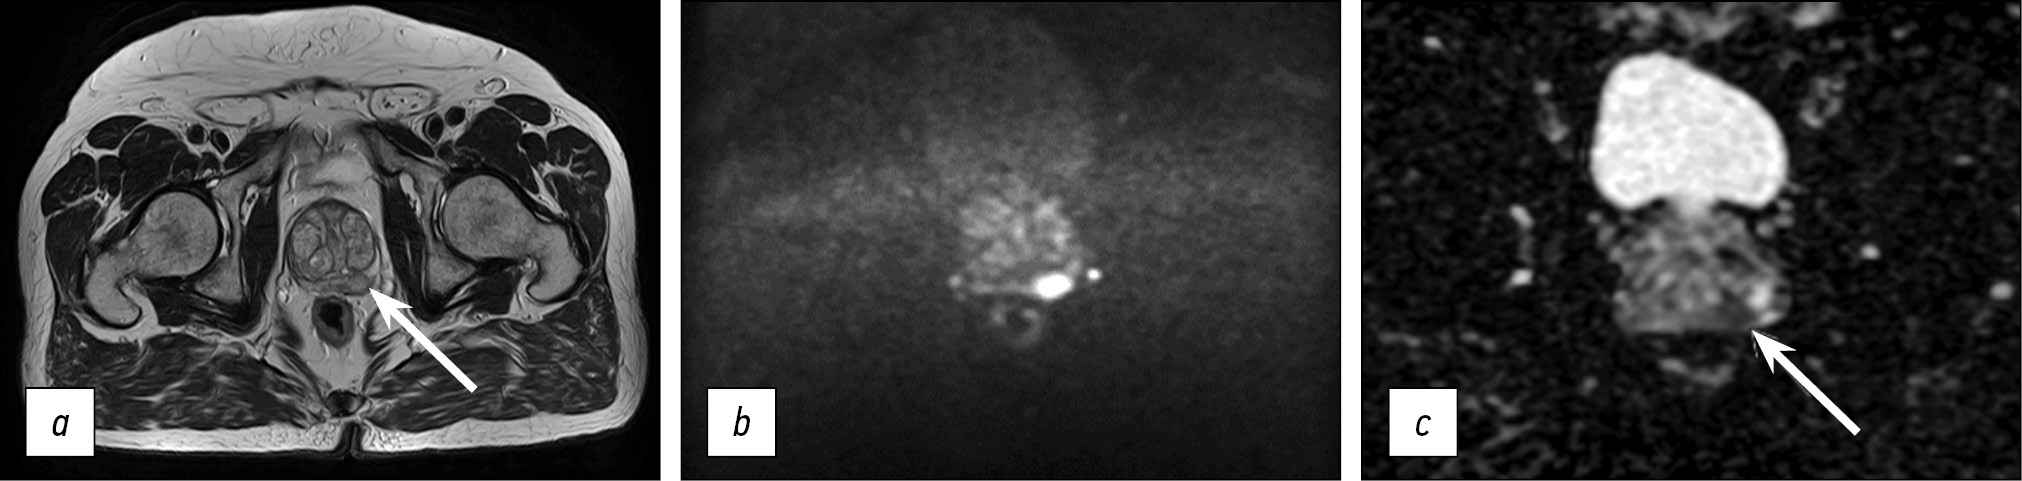

The resulting protocol provides a sufficiently high level of visualization quality. Fig. 5 presents images obtained using the optimized protocol. The total scanning time was less than 11 min.

Fig. 5. Images obtained using the accelerated protocol of biparametric magnetic resonance imaging. Patient with prostate changes consistent with PI-RADS 2: a) T2-WI, axial view; b, c) DWI and ICD.